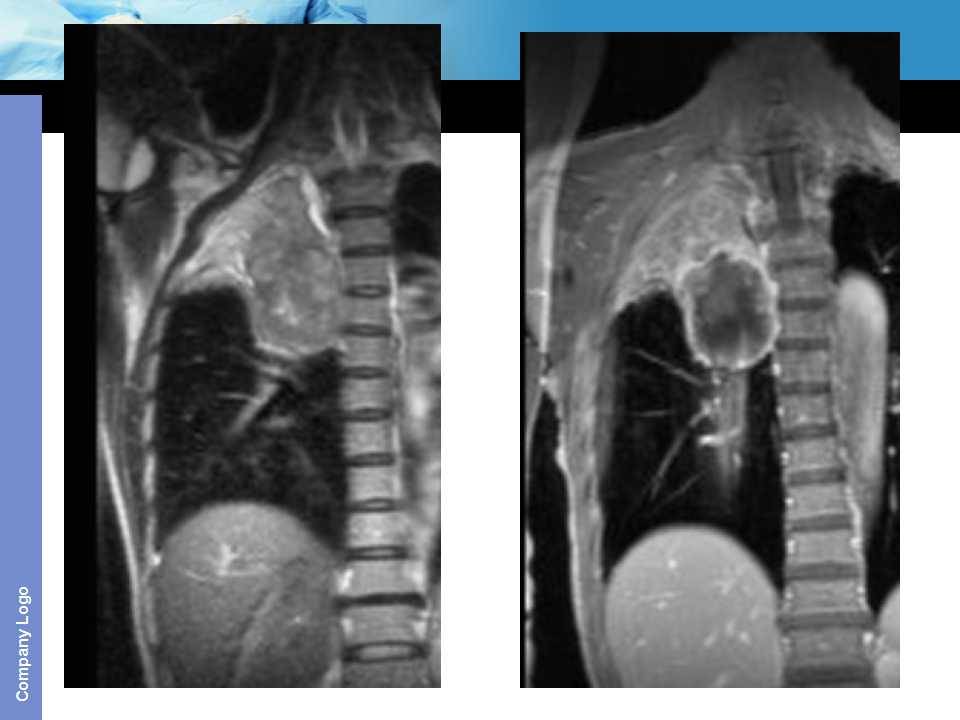

肺癌影像诊断